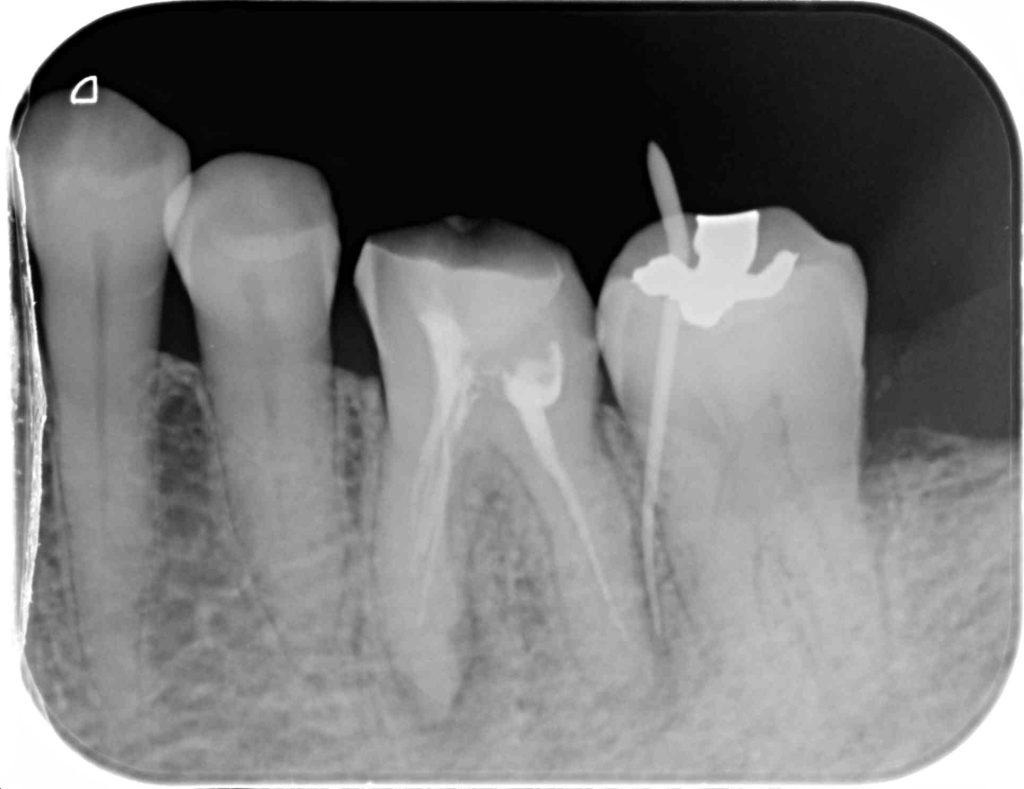

下記の症例は奥歯の抜歯と同時にインプラント治療を行った術後になります。

安全なインプラント治療を提供する為に、SMOPガイドシステムを活用し、術中の痛みやストレスをコントロールする為に麻酔科医による鎮静麻酔を依頼しました。